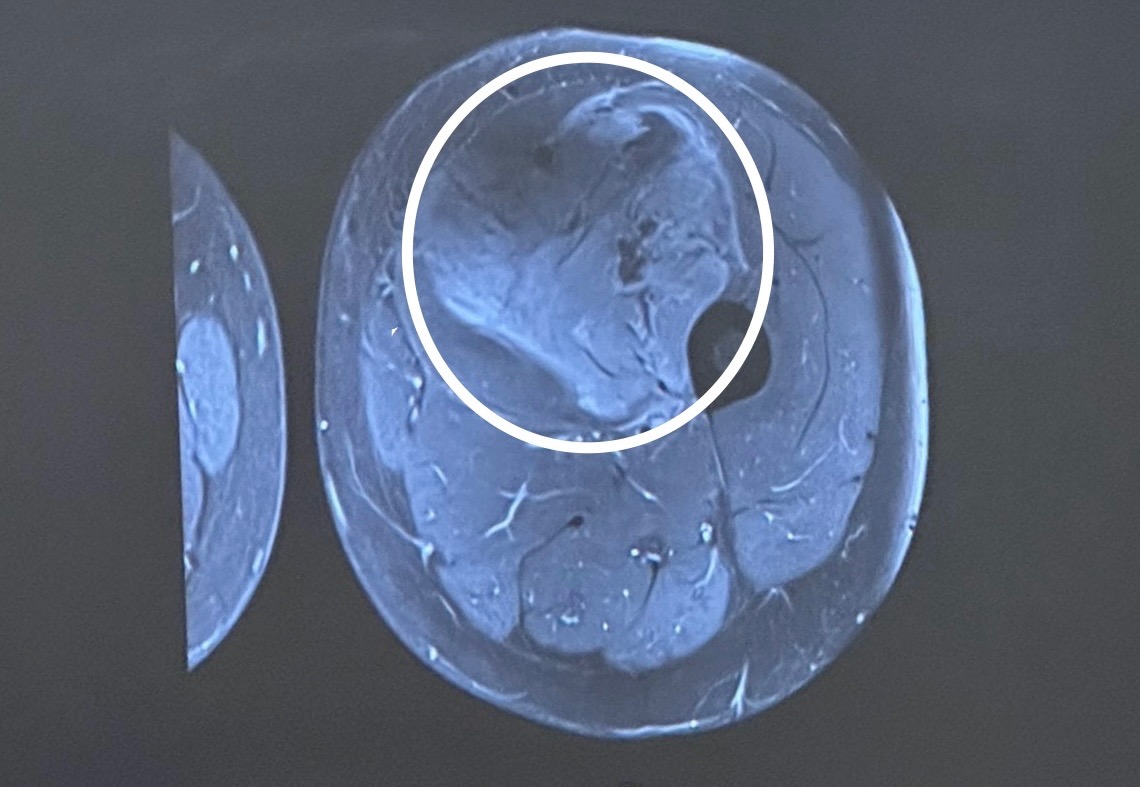

Hi everyone, my name is Aurora and my sweet boyfriend Blake Dore has recently been diagnosed with a Synovial Soft Tissue Sarcoma, a rare form of Cancer found in less than 1% of cancer cases. It is a 12cm tumour growing in his thigh, wrapping around his muscles and artery. It is chemo resistant and can only be treated with radiation and surgery. He will undergo 25+ radiation treatments here in Sudbury and have surgery in Toronto in the weeks following. We are looking for financial support during this time to go toward our travels to Mount Sinai Hospital in Toronto for surgery and recovery. Fertility expenses due to radiation side effects and general health related bills. As a young couple living on our own we are overwhelmed by the potential costs. Anything helps and we appreciate it so much. Thank you.